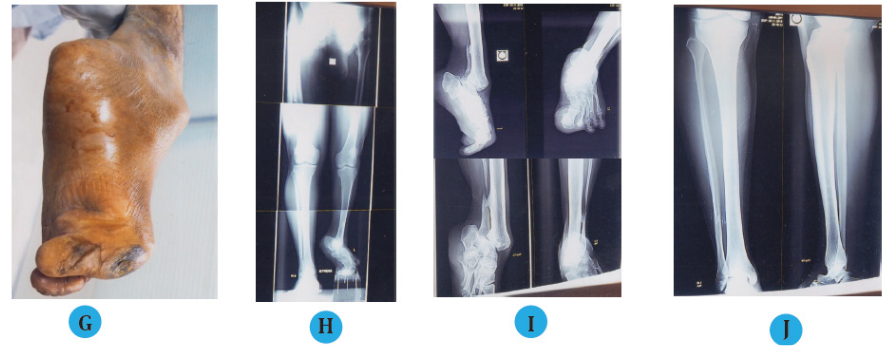

(G) Hard and discolored skin over the dorsum of the great toe.

(H) Stress radiographic view of lower limb with post septic equinus deformity of left ankle with 7 cm LLD, with 90° downwards displacement of great toe.

(I) Radiographic view of equinus ankle and 90° downwards displacement great toe.

(J) Radiographic view of normal right tibia and ankle for comparative study.